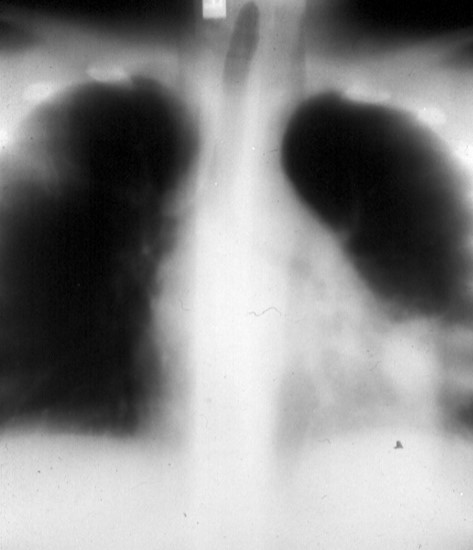

Patient C: A 24-year-old woman with acute myelogenous leukemia who developed fever,

rigors and progressive dyspnea while on chemotherapy.

In panels B and C cryptococcal pneumonia was accompanied by cryptococcal fungemia.

Both patients had impaired cell-mediated immunity, in patient B due to his paraneoplastic

Cushings syndrome, and in patient C due to her chemotherapy-induced leukopenia. These

patients received intravenous amphotericin B but, unfortunately, both expired despite

treatment.

C.

Bilateral C. neoformans fungemic pneumonia in a

neutropenic patient with AML.